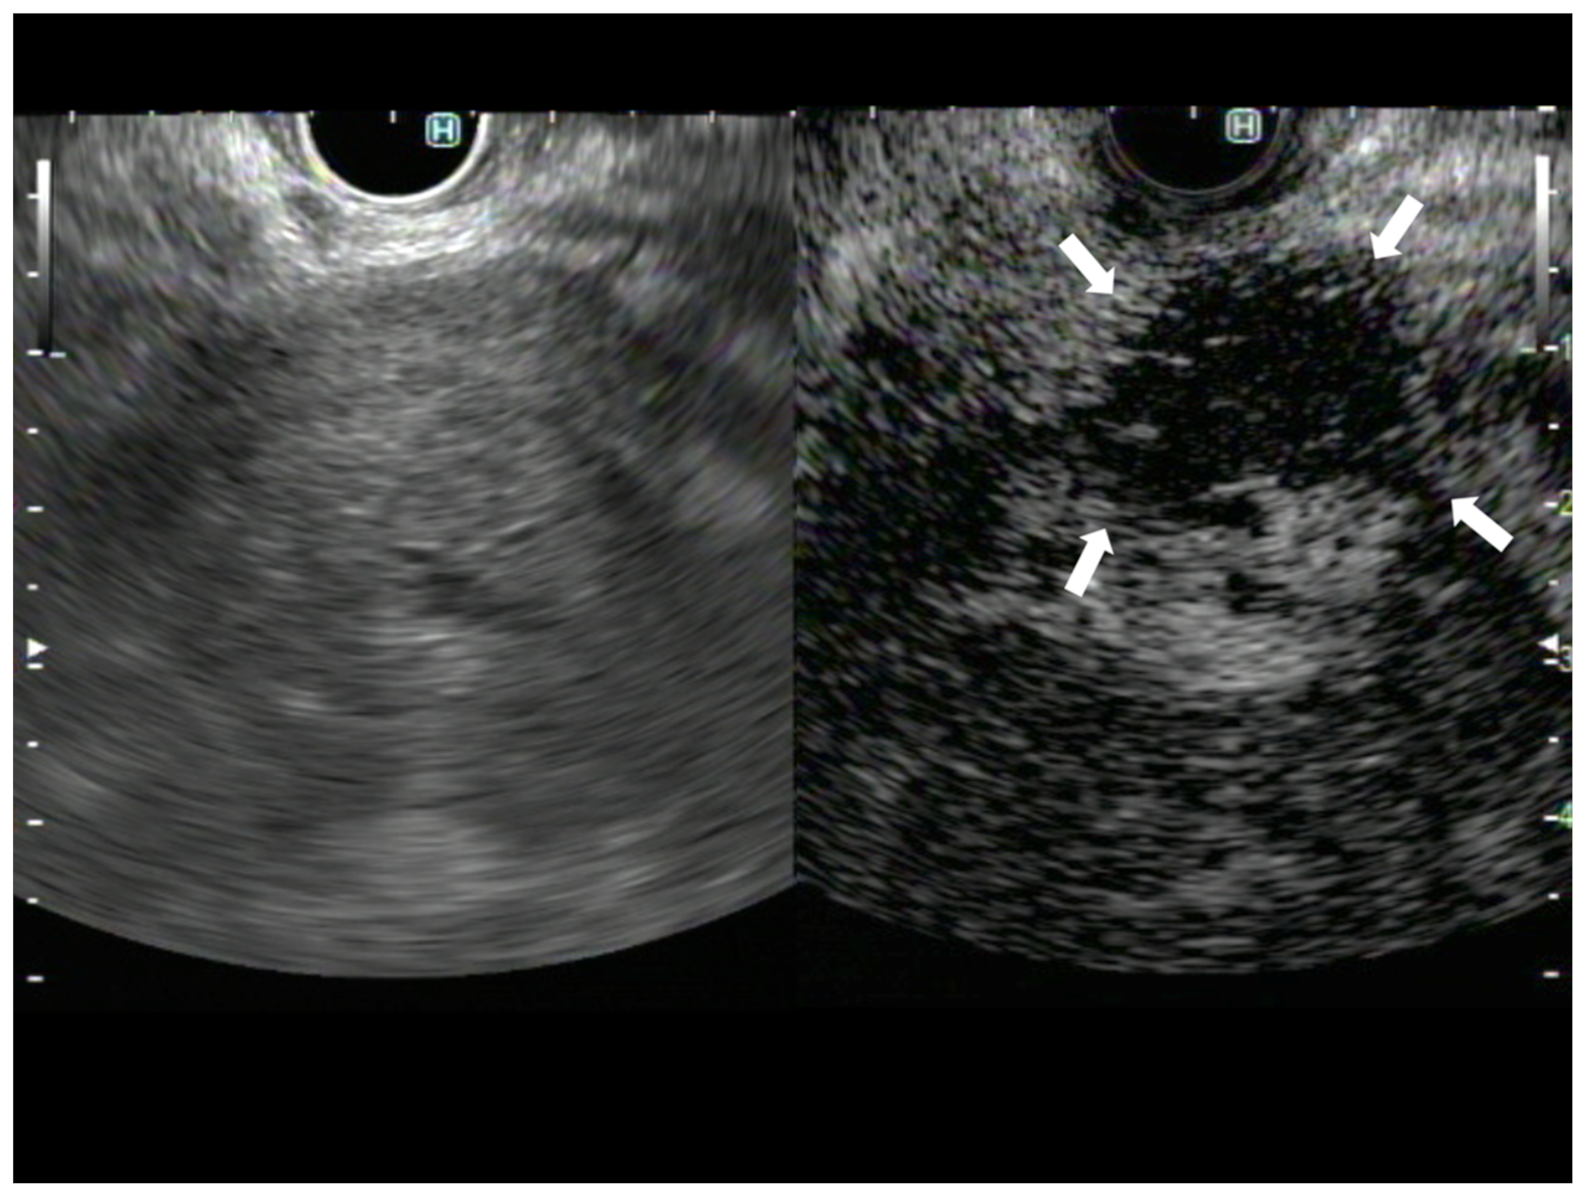

3. Avascular Areas on CH-EUS

- Kamata, K.; Takenaka, M.; Omoto, S.; Miyata, T.; Minaga, K.; Yamao, K.; Imai, H.; Sakurai, T.; Nishida, N.; Chikugo, T.; et al. Impact of avascular areas, as measured by contrast-enhanced harmonic EUS, on the accuracy of FNA for pancreatic adenocarcinoma. Gastrointest. Endosc. 2017, 87, 158–163. [Google Scholar] [CrossRef] [PubMed]